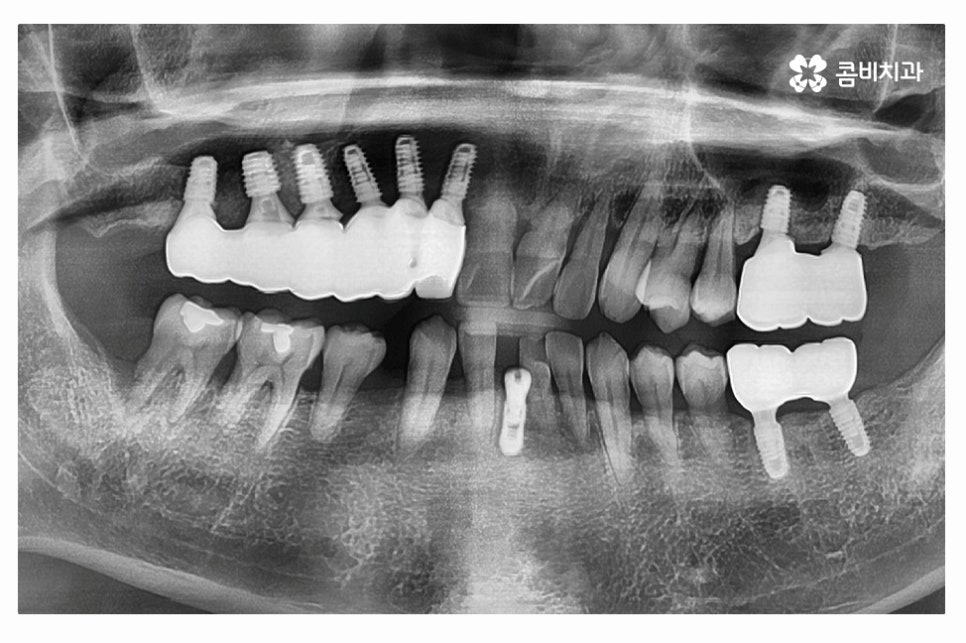

치주질환으로 인해 치아의 상당수를 한꺼번에 잃게 되면

임플란트의 저작력이 분산되는 것이 임플란트 수명 유지나

저작력의 부담을 줄이기에 유리하기 때문에

현재 구강 상태에 맞춰 1:1 맞춤 치료 계획을 세울 필요가 있어요.

임플란트를 위 사례처럼 여러 개를 식립할 경우에는

크라운을 여러 개를 이어 붙이게 되며 보통은 3~4개 정도 연결할 수 있고

4개가 넘어갈 경우에는 나눠서 연결하고 크라운을 씌우는 과정을 거칠 수 있어요.